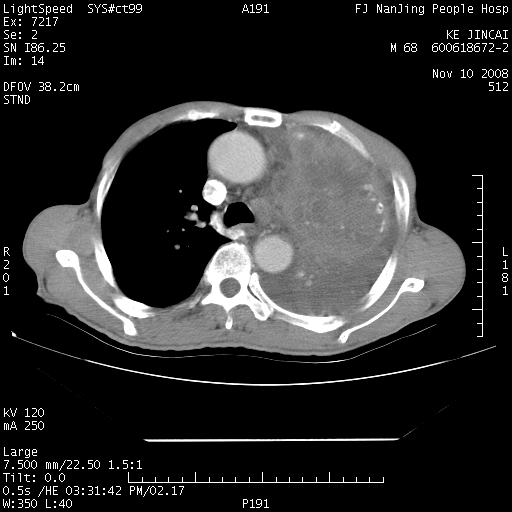

是个很有看头的病例,咋人气那么不旺?没多少人兴趣呢?这个病例几大怪:1   恶性肿瘤侵犯心肌左房怪,心肌一般不会被恶性肿瘤侵犯吧?2   左下肺均匀实变怪,内无含气,有别一般不张实变,含气肺泡完全为液体取代,而非一般不张实变的肺萎陷,冷不丁还以为是肿大的脾脏3   肿瘤本身怪,像tb肺不张4   这么有看头的病例没人气怪。呵呵。

左肺恶性肿瘤侵犯肺动脉,左心房内瘤栓,胸膜转移。